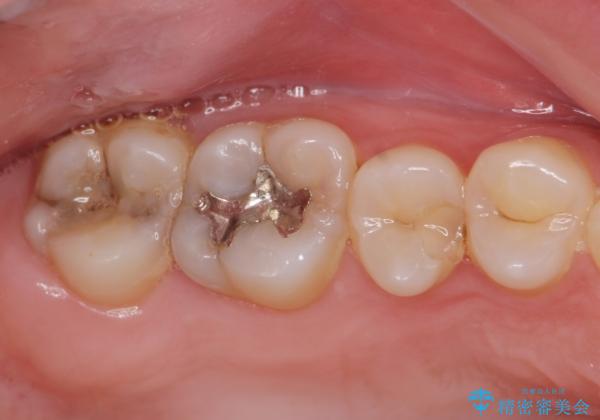

奥歯の虫歯の治療

- 奥歯が虫歯になっていたため治療しました。

手前側の歯は前から見えるため、セラミックの詰め物で治療しました。

奥は高さを取るのが難しかったため薄く作れる金属(ゴールド)で治療しています。

- 合計 26.4万円(内訳:右上7 PGAクラウン 11万円(旧料金)、右上6PGAインレー 7.7万円(旧料金)、右上5 emaxインレー 7.7万円)費用は治療当時の料金となります

今後の虫歯予防に、治療と合わせて歯磨き指導も行っているため、清掃状態も大きく改善しています。